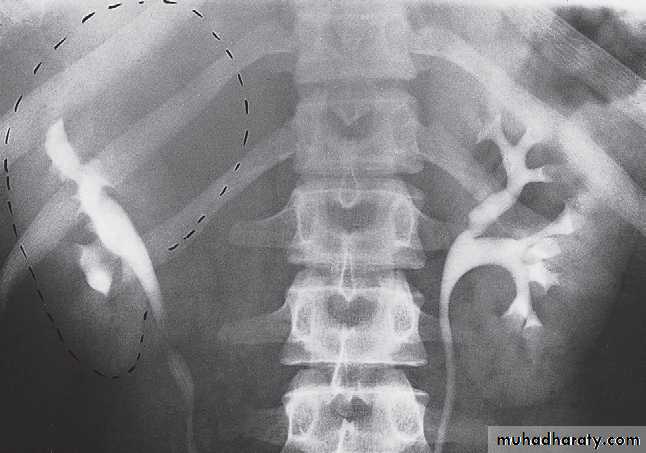

Ectopic kidney

During fetal development the kidneys ascend within the abdomen. An ectopic kidney results if this ascent is halted. They are usually in the lower abdomen and rotated so that the pelvis of the kidney points forward. The ureter is short and travels directly to the bladder. In some cases, both kidneys lie on the same side of the pelvis and are fused.Horseshoe kidney

The kidneys may fail to separate, giving rise to a horseshoe kidney. Almost invariably it is the lower poles that remain fused .Inherited cystic disease of the kidneys